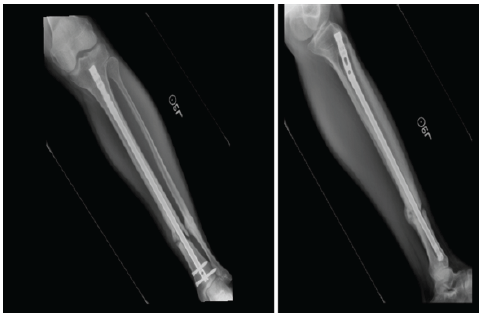

Figure 2: Radiographs identified that there was a non-union or pseudoarthrosis associated with the tibia, but there was healing associated with the fibula. The proximal interlocking screw removal is identified with the lack of a screw proximally.

At 4 months, radiographs demonstrated delayed union, as noted in Fig. 2. The proximal interlocking screws were removed to allow dynamization. Six months later, persistent non-union was present, with continued pain and difficulty bearing weight. He subsequently underwent exchange intramedullary nailing with interlocking, fibular osteotomy, local bone grafting, and debridement of the pseudoarthrosis site. Despite these procedures, serial radiographs over the following months showed no evidence of progressive healing, as seen in Fig. 3.